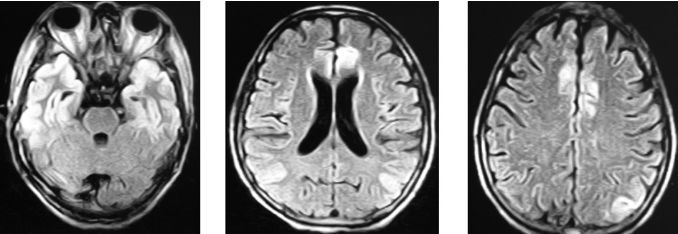

图2头颅mri:双侧额颞枕叶可见长t2(图2),flair呈高信号异常(图3).

flair 示双侧额叶内侧,岛叶皮层和尾状核内信号改变(圈示).

第9日行头颅mri示:双侧额叶皮层(图1),双侧丘脑,下丘脑,第三脑室,中脑

图 1.(a,b 和 d)脑 mri 显示双侧额叶萎缩.(c)颞叶是正常的.